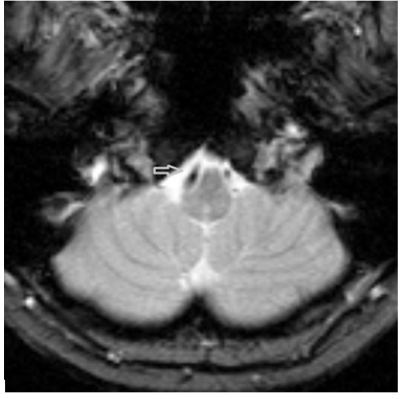

Native cerebral magnetic resonance imaging examination has revealed four features: normal MR signal of the brainstem; dominant and sinuous right vertebral artery (VA) compressing junction between medulla oblongata and spinal cord; medulla oblongata clamping in between the two vertebral arteries; and loss of foramen magnum cerebrospinal fluid (CSF) spaces due to low lying cerebellar tonsils tips, while cisterna magna is still visible. Figure 1 depicts the VA compressing right ventrolateral junction of medulla oblongata with spinal cord. Figure 2 reveals the medulla clamping in between the two vertebral arteries.

According to our knowledge, this is the first reported case of HAS due to a dilated or sinuous VA. A sinuous VA compressing the medulla oblongata – spinal cord junction may compress the VRG which contains both inspiratory and expiratory neurons, as well as neurons which control larynx and pharynx muscles.